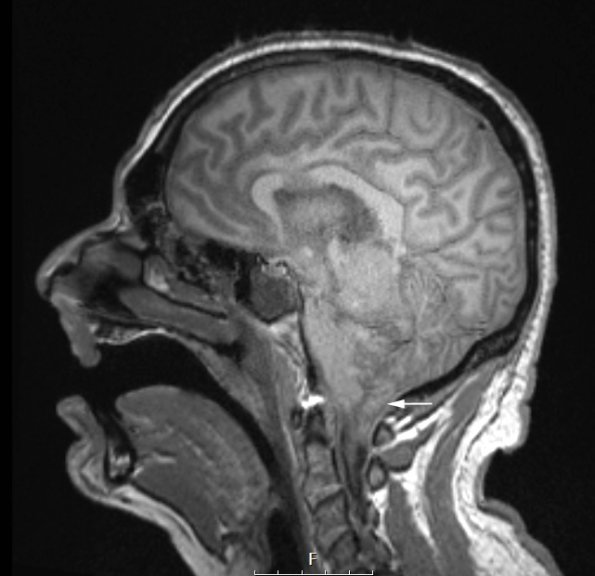

This sagittal T1-weighted scan without contrast shows cerebellar tonsillar herniation (arrow).